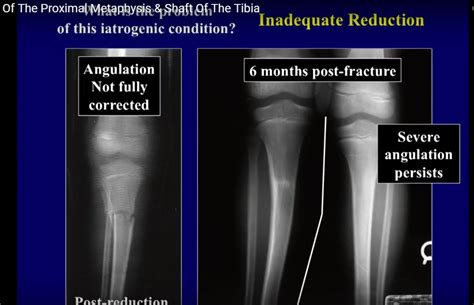

Fracture Of Tibia / Radiographs of Tibia Fibula Fracture | Bone and Spine / To diagnose a fractured tibia, a doctor will ask about a person's medical history and how the injury happened.

Fracture Of Tibia / Radiographs of Tibia Fibula Fracture | Bone and Spine / To diagnose a fractured tibia, a doctor will ask about a person's medical history and how the injury happened.. I estimate that after four to six weeks, your doctor will start physical therapy that. Diagnosis is confirmed by orthogonal radiographs of the tibia and adjacent joints. Tibial shaft fractures, which occur between the knee and ankle joints, are the most common type of tibia fracture. When there is a fracture of tibia and fibula which is strong enough to break the bones but not strong enough for the bones to penetrate out of the skin is what we term as closed tibia or fibula fracture. A broken tibia can be a variety of complex injuries, that often.

The annual incidence of open fractures of long. They are normally caused by trauma such as a sports injury, or a fall at home or work. When there is a fracture of tibia and fibula which is strong enough to break the bones but not strong enough for the bones to penetrate out of the skin is what we term as closed tibia or fibula fracture. Diagnosis is confirmed by orthogonal radiographs of the tibia and adjacent joints. There are several complications of this injury that could make them potential emergencies.

Undisplaced tibial shaft fractures should be put in an above knee backslab and followed up in the orthopaedic fracture clinic in 1 week. In 673 open fractures of long bones (tibia and fibula, femur, radius and ulna, and humerus) treated from 1955 to 1968 at hennepin county medical center, minneapolis, minnesota, and analyzed. A tibia shaft fracture is one of the most common long bone fractures, with two general types, open fracture and close fracture. Tibial stress fractures are most often found in distance runners, in whom normal bone is subjected to repetitive longitudinal stress fractures of the tibia: Fractures of the tibia may result from significant trauma or be the consequence of repetitive use. Lower leg fractures include fractures of the tibia and fibula. A triplane fracture of the distal tibia usually occurs during. Fractures of the tibia are often associated with fracture of the fibula (displaced fractures usually involve both the tibia and fibula). Some tibial shaft fractures can be treated in a long leg cast. People are generally unable to walk. Tibia fractures are the most common lower extremity fractures in children. Suffice it to say here. Treatment for tibia and fibula fractures ranges from casting to surgery, depending on the type and severity of the injury.